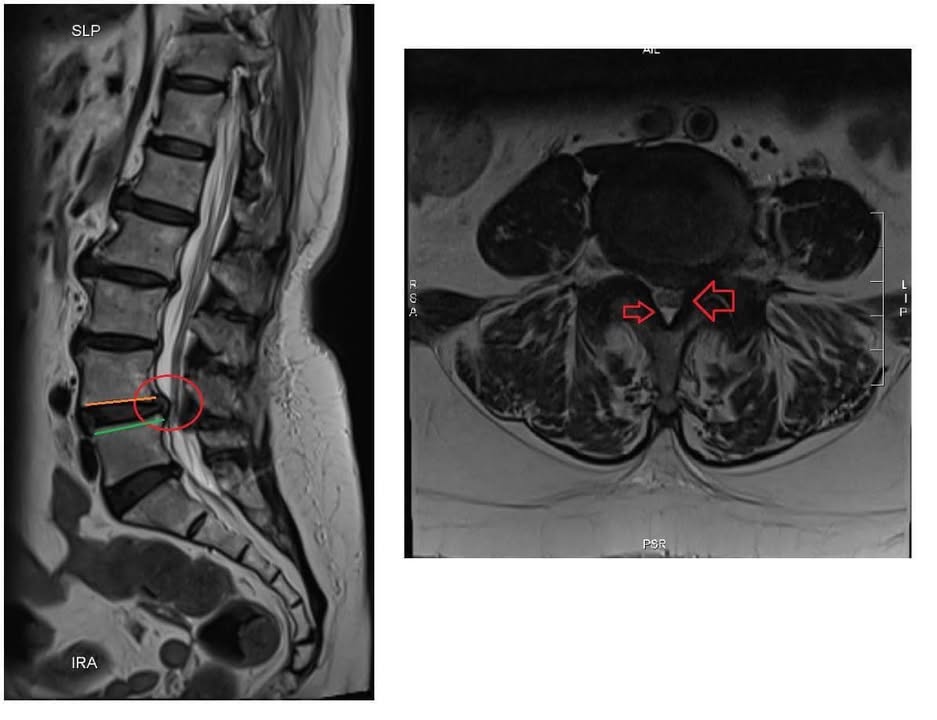

Cervical Spine Treatment Cases 腰椎治療案例 #今天來聊巨大骨刺為何可以吸收回去! #椎間盤突出需要多久才能吸收呢? #馬尾神經症候... 2020.09.08 #典型假性坐骨神經痛 #原來是梨狀肌症候群 #核磁共振排除椎間盤突出 #抽絲剝繭真相大... 2020.08.13 #嚴重椎管狹窄醫案 #感謝台北林大哥熱情見證 #從寸步難行到輕快漫步 #鍛鍊多裂肌的重... 2020.08.12 #椎間盤突出可以吸收回去嗎 #微針治療原理是什麼 #何時一定要接受神外開刀 #一張圖秒... 2020.08.11 #感謝花蓮鄉親林大姐熱情見證 #一分鐘認識椎管狹窄 #原本痛到無法走路打算開刀了 #脊... 2020.08.01 #感謝新莊區林先生熱情見證 #椎間盤突出跟纖維環裂隙的關係 #纖維環破裂突出可以不... 2020.07.28 #逆轉勝又一發case #原本疼痛一年多想說一定要手術治療了 #八週治療後症狀全部消失 #... 2020.07.25 #巨大椎間盤突出一定要開刀嗎 #除了開刀以外的選擇 #感謝台北市吳先生熱情見證 2020.07.24 #腰椎滑脫的疼痛心酸誰人知啊 #一分鐘瞭解腰椎滑脫 #哪一種情況需要積極開刀 #要如何... 2020.07.21 #巨大椎間盤脫垂一定要開刀嗎? #感謝新店林先生熱情見證受訪 #西醫手術有那些選擇... 2020.07.02 #纖維環裂隙AnnularFssures #MRI看起來不嚴重卻嚴重困擾患者 #感謝桃園市蕭先生熱情見... 2020.06.19 #骨刺有可能吸收回去嗎?? #疼痛超過六年的特殊案例探討 #MRI核磁共振前後對比 #感謝... 2020.06.14 #坐骨神經痛一定要開刀嗎 #突出的骨刺真的可以自己吸收嗎 #最新英國醫學期刊BMJ的看... 2020.05.30 #骨刺跟突出髓核有可能吸收回去嗎?? #特殊案例探討 #核磁共振一年後對比 2020.05.29 #從醫以來第一次碰到薦椎Tarlov cyst囊腫#左邊紅色圈圈是個案,右邊是國外案例#腰... 2020.05.23 ← 上一頁 10 11 12 13 14 下一頁 →